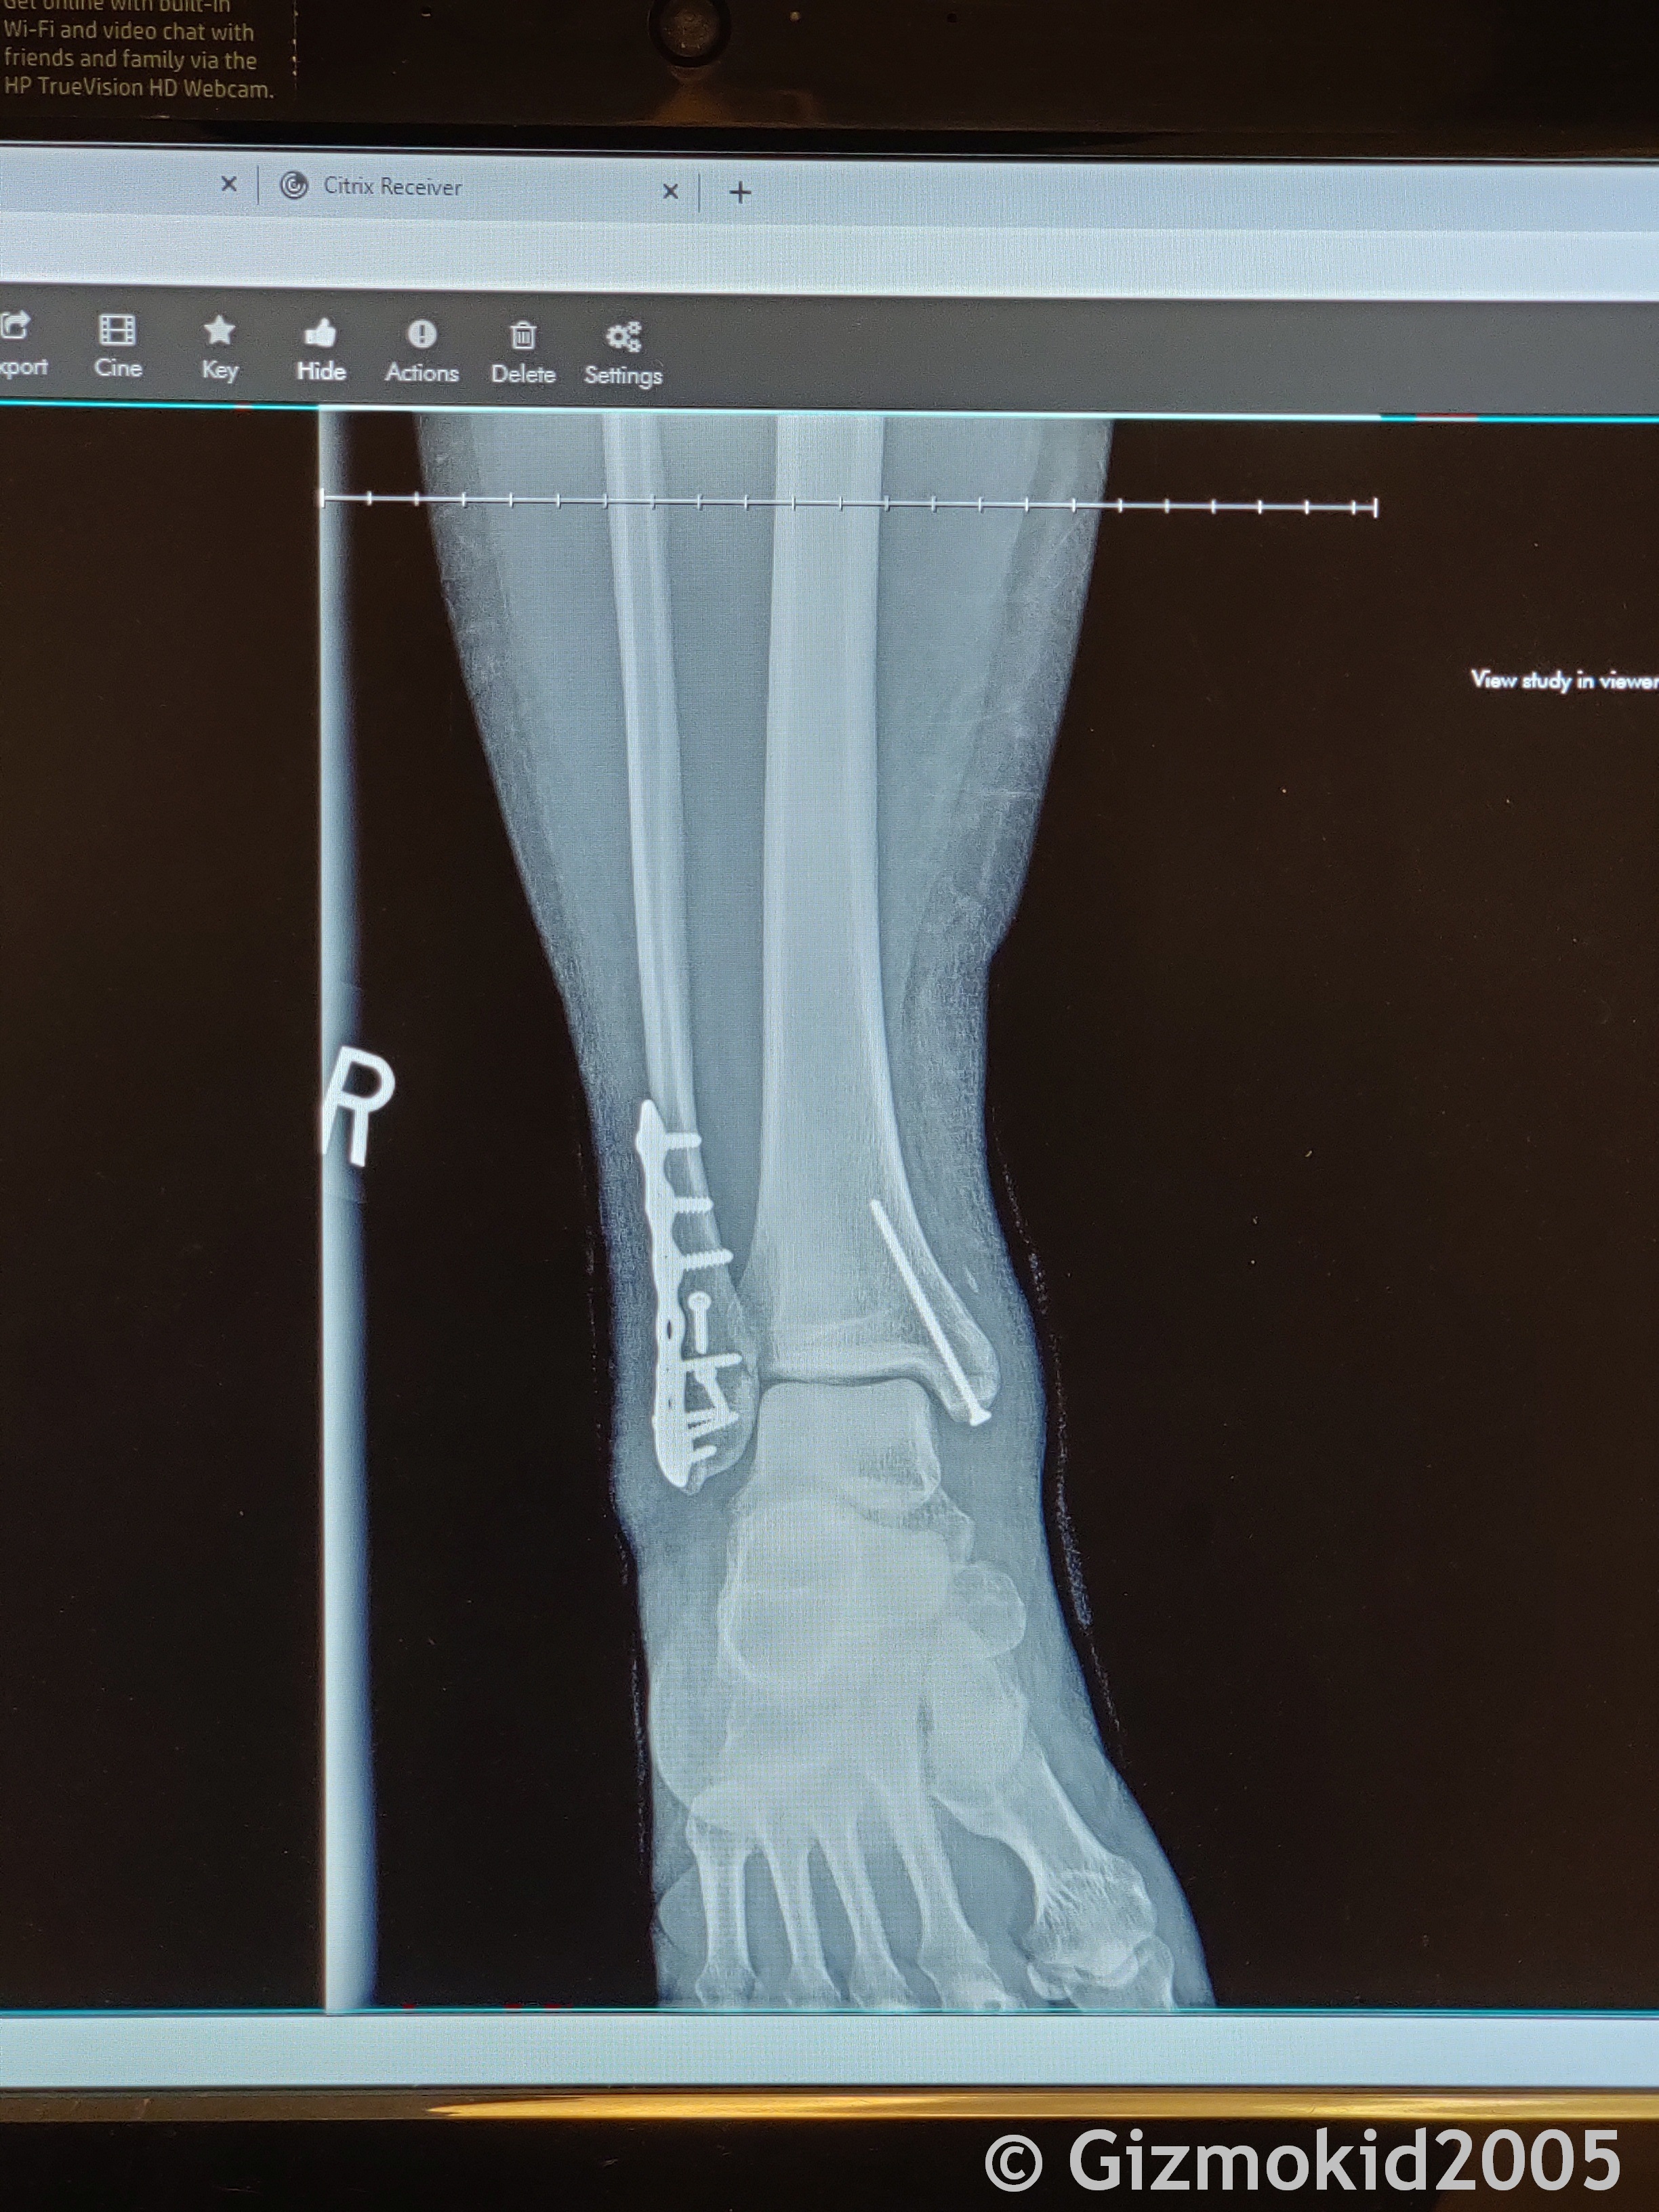

I had ankle repair surgery on December 11th, and have approximately a 6-8 week recovery until I can be truly weight bearing again, with up to 16 weeks until I'm no longer assisted by any devices (including splint). I'm lucky that in almost 30 years of all my shenanigans and being a monkey, off-roading, biking, etc, this was the first time I've really ever injured anything.

And here's the xrays of what they had to do to put my ankle back together again.